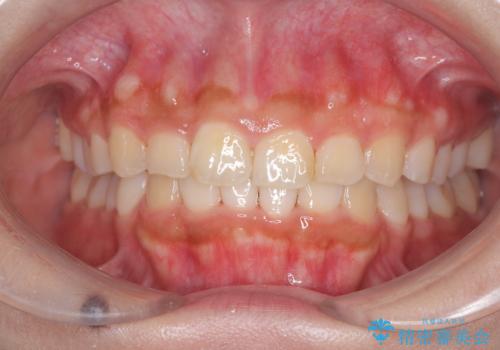

[マルチブラケットで後方移動] ワイヤー矯正で行う噛み合わせの改善